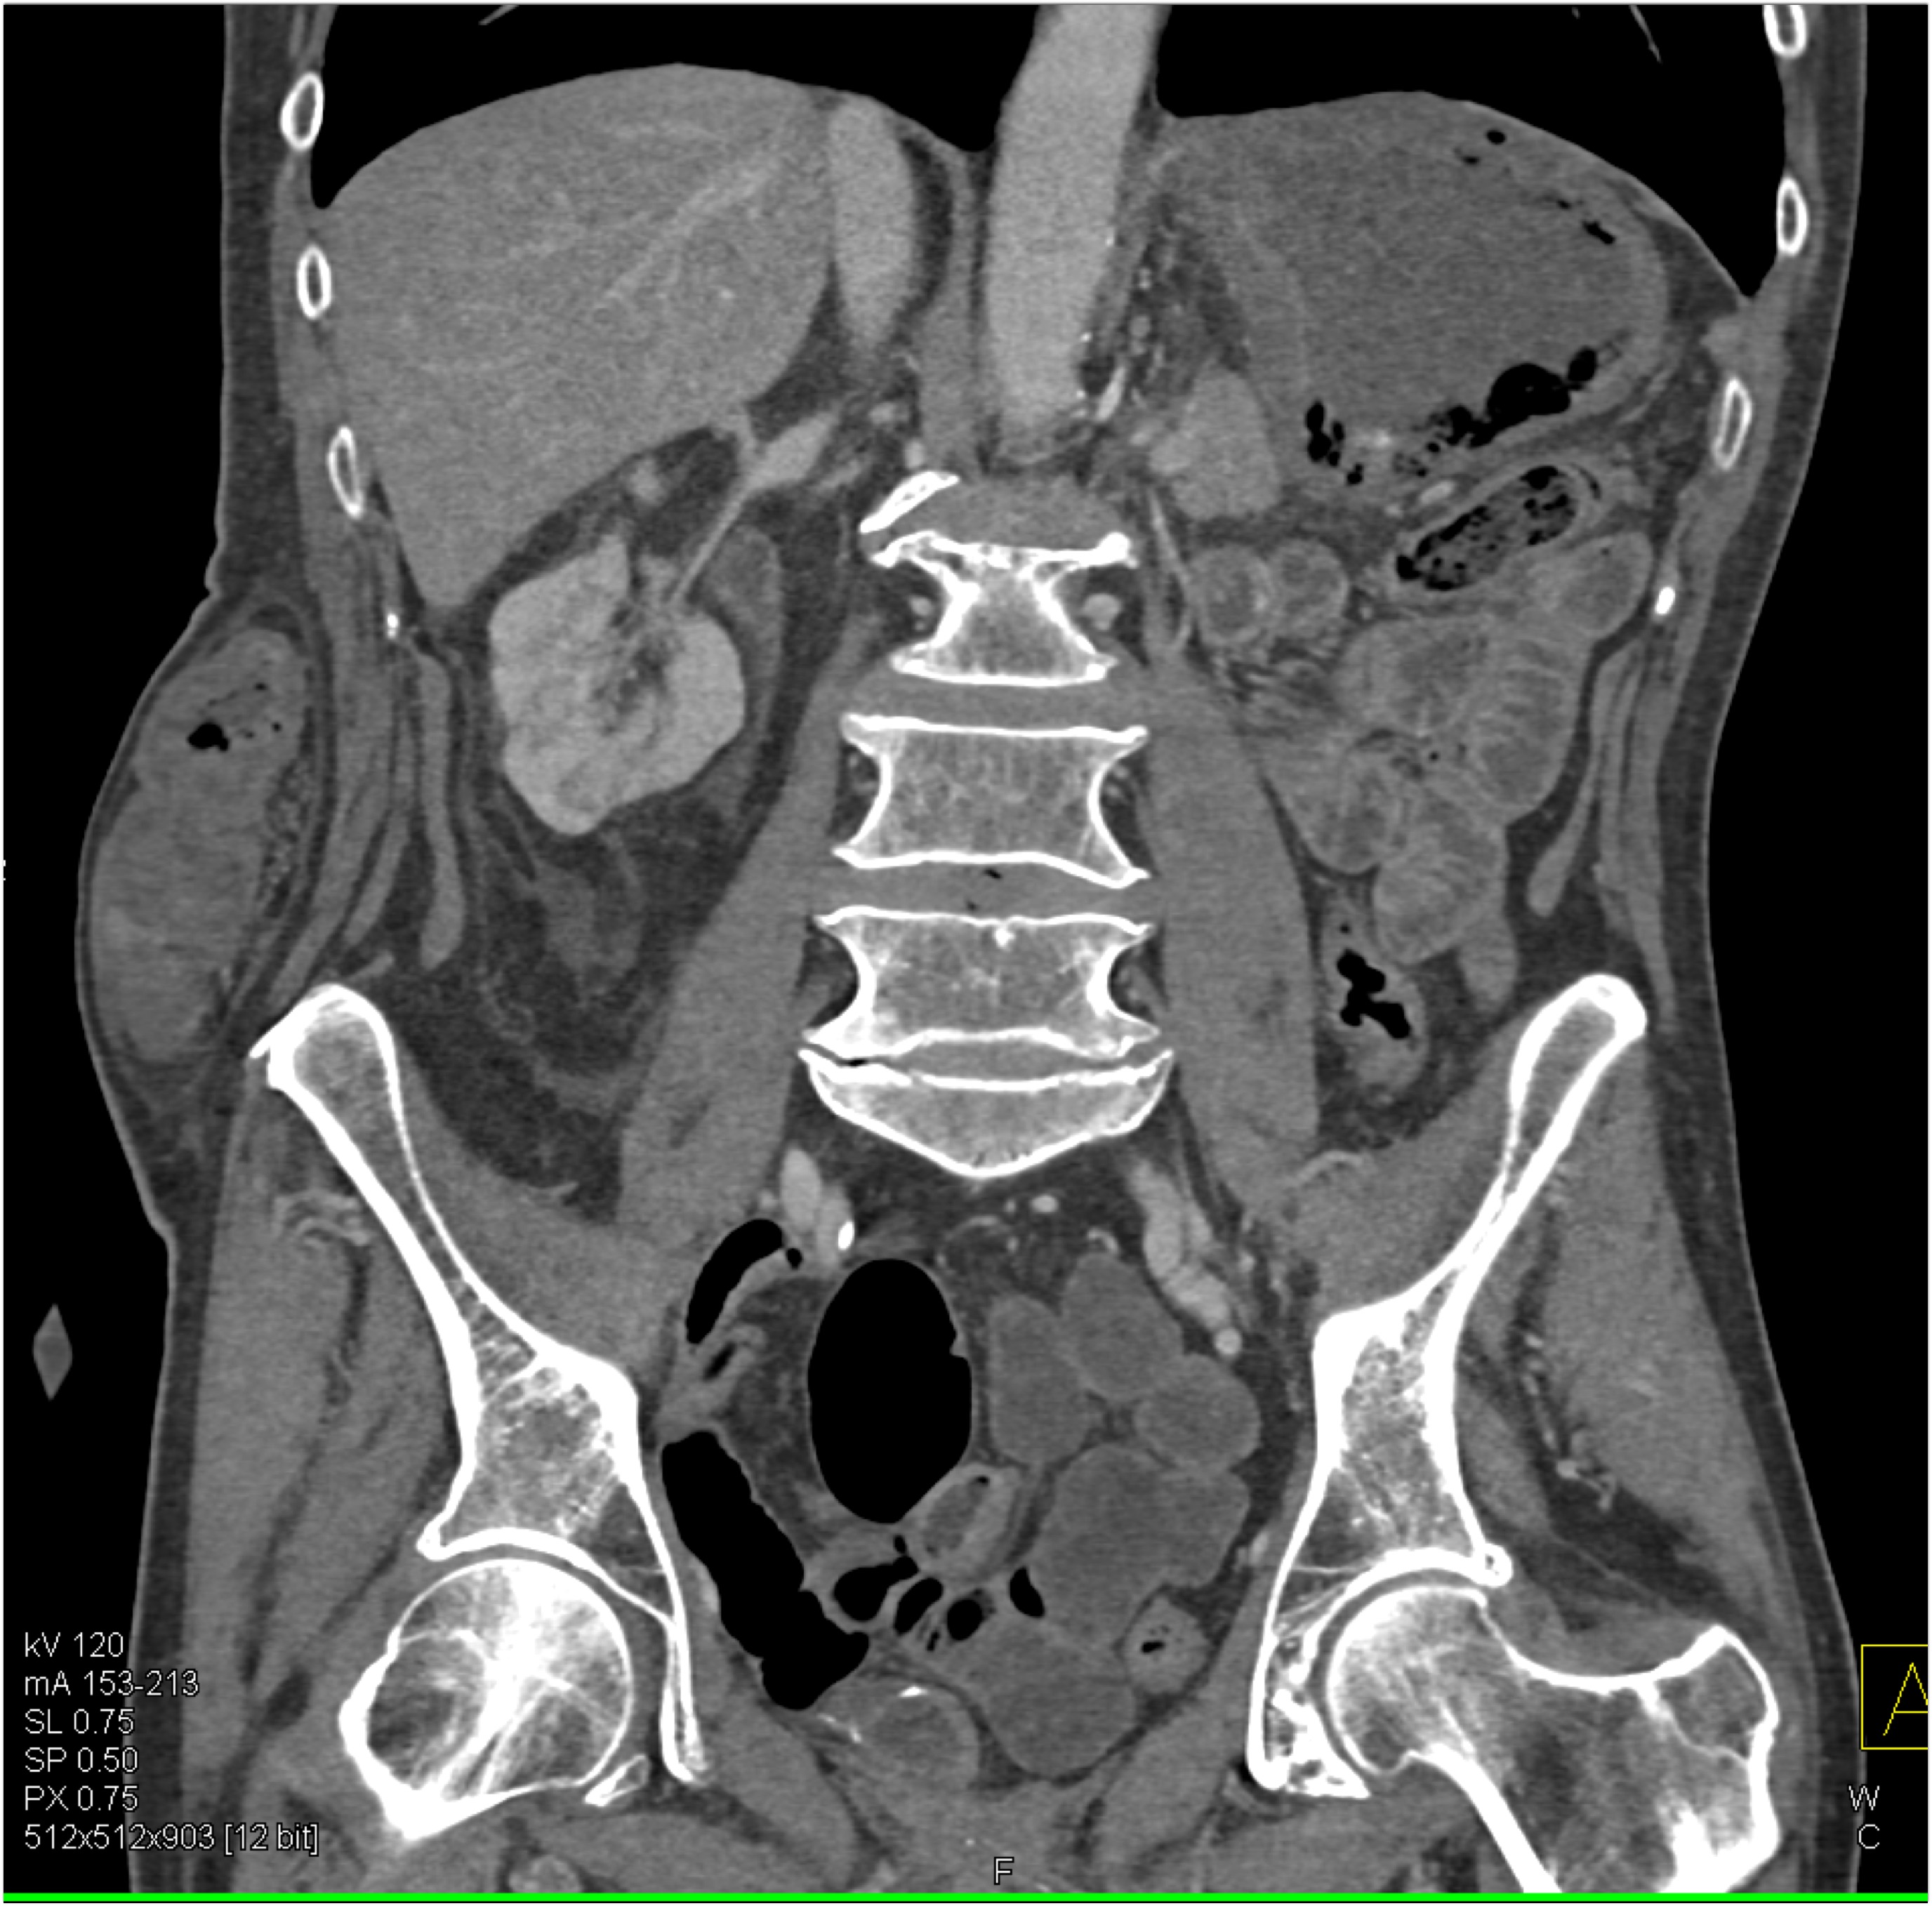

2) In this patient on dialysis for ESRD the best diagnosis is?

normal bypass graft

AV fistulae with aneurysms

vasculitis

infectious vascular disease